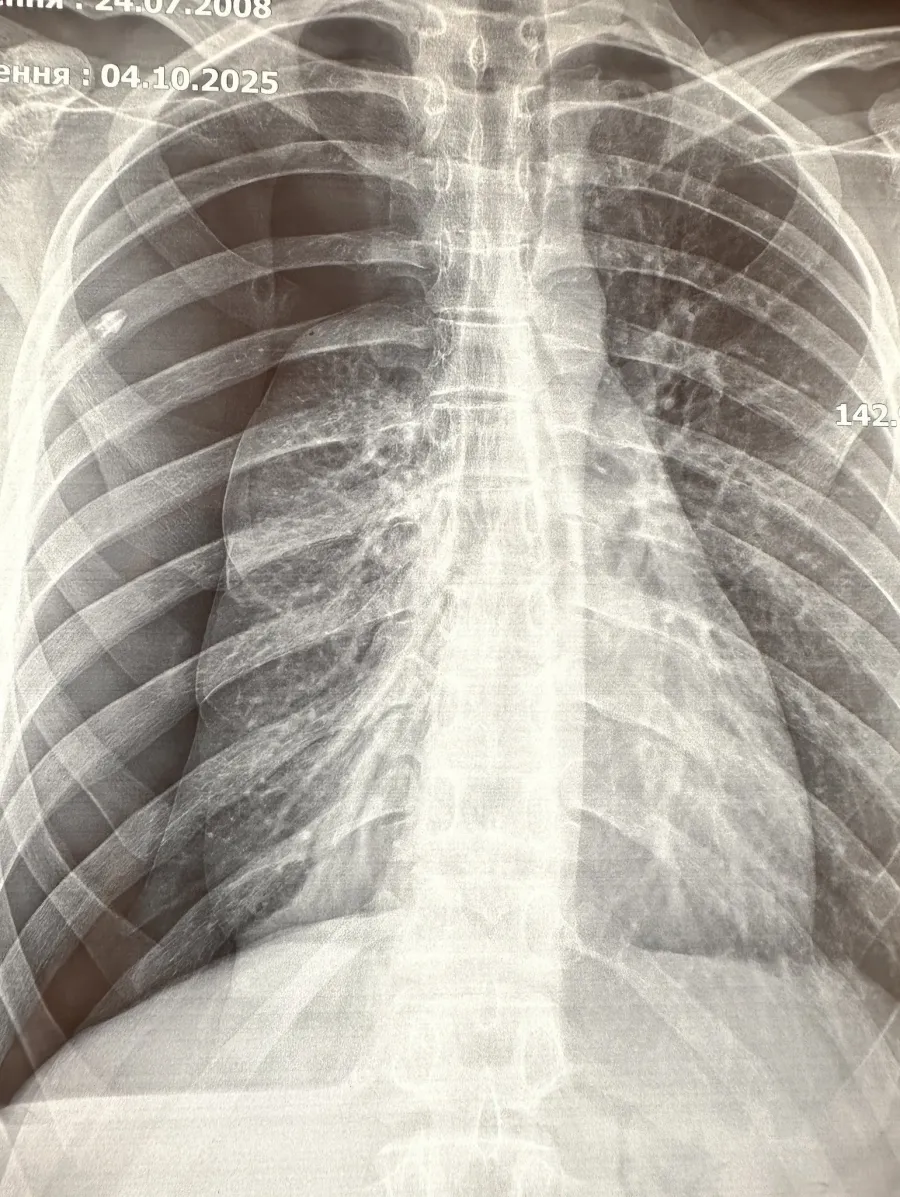

При дообстеженні встановлено діагноз: бульозна хвороба правої легені, правобічний пневмоторакс.

Після цього вперше в ОДКЛ провели малоінвазивну операцію — торакоскопічну резекцію ураженого сегменту правої легені. Оперативне втручання провела команда у складі хірурга Ореста Бориса, хірурга І ТМО міста Львова Андрія Дворакевича та анестезіолога Андріани Гончар.